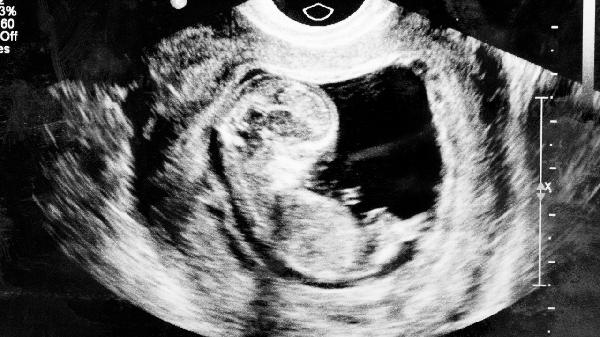

子宫肌瘤在B超下呈类圆形低回声团块,可测量肌瘤数量、大小及位置。子宫内膜增厚伴不均匀回声需警惕内膜病变。卵巢囊肿根据回声特点可区分生理性囊肿与病理性肿物。早孕期间B超能确认孕囊位置、胚胎心管搏动等情况。